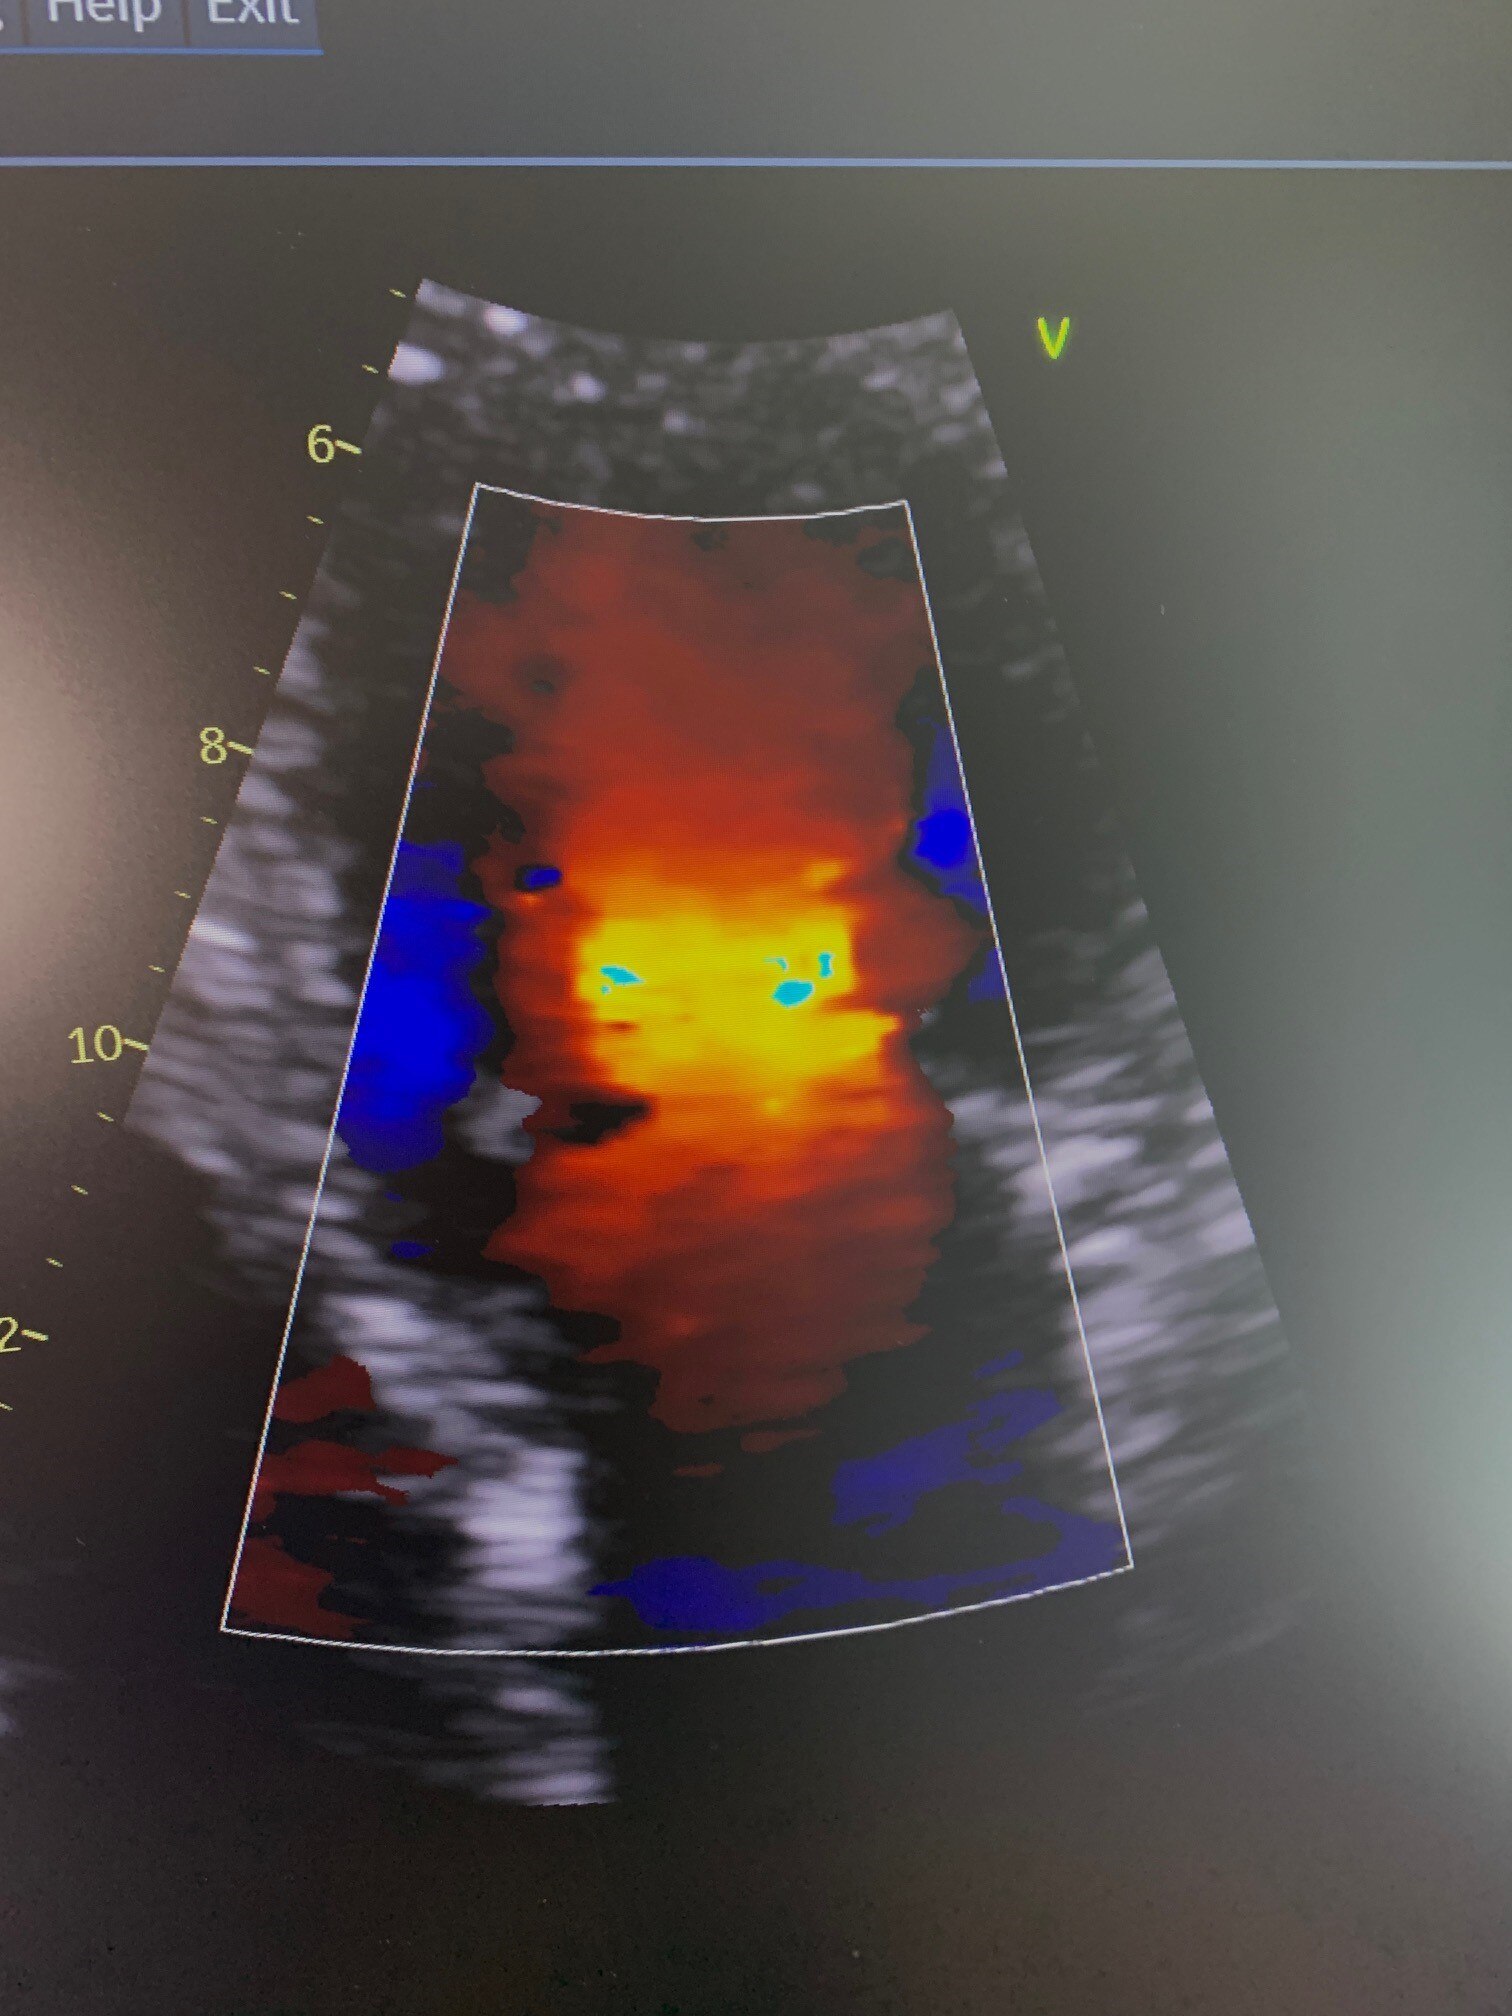

Instead, Ms O'Keefe is being guided by artificial intelligence as she performs the echocardiogram, the ultrasound of the heart.

The AI software prompts Ms O'Keefe on where she needs to hold the ultrasound probe, and how much pressure to apply, depending on what the echocardiogram is looking for.

A man undergoes an echocardiogram in Alice Springs Hospital with the aid of artificial intelligence.  (ABC News: Steven Schubert)

The ultrasound images help cardiologists diagnose heart problems in patients hundreds of kilometres away. (ABC News: Kyle Harley)

The images are uploaded to a cloud-based server,and then downloaded and analysed by cardiologists. who may be hundreds of kilometres away from the patient.

The artificial intelligence program tells the ultrasound operator how to get a usable picture of a heart.  (ABC News: Steven Schubert)